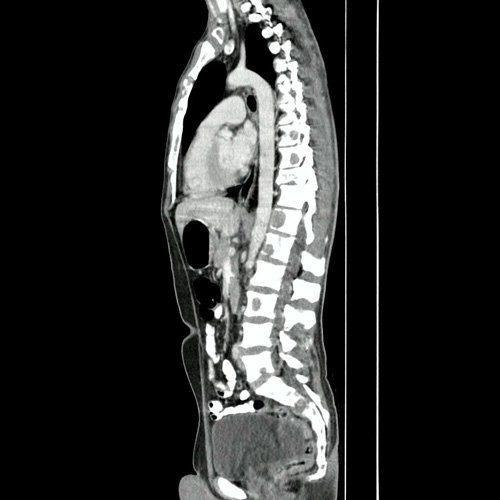

TAC de tórax con contraste EV (Corte axial): Presenta lesión de densidad partes blandas, paraespinal derecha, en el espesor de los músculos lumbares y en contacto también con el psoas homolateral, de limites mal definidos ,con refuerzo tras el contraste y

TAC de tórax con contraste EV (Ventana pulmonar- corte axial): En el parénquima pulmonar, a nivel del segmento apical del LIl se observa una consolidación asociada a una voluminosa imagen quística de paredes delgadas, multiloculada y aparentes bronquiecta